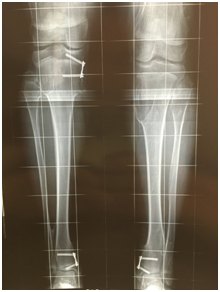

2.治疗 关于治疗,又有一些病友咨询,能否通过“绑腿带”给矫正过来?我的回答是:NO。膝内、外翻一般都是骨性畸形,也就是说是骨骼的变形,骨骼在生长过程中长弯了。我们都知道骨头是硬的,那么一段硬的弯的骨头,你能把它绑直了吗?至少当代的医学技术还没有达到这个水平。所以,对于成年人来说,只能通过手术,将长弯的骨头截断,然后把它矫正直了再固定起来,等截断的骨头长好了,腿就直了,但别小看了这个截断骨头再接起来了手术,有很多的技巧和内涵,不是随便就能截好和接好的。但是对于生长期的儿童来讲,就不一定需要截骨了,现在有一种很神奇的钢板叫做8字钢板,也就是一块有两个孔的金属(现在多用钛合金材料)板,形状像数字“8”;从X线片上看,儿童腿骨的两端各有一条缝,叫骨骺(hou),这条缝就是骨头长长的地方,如果这条缝均匀的生长,骨头就是直的,如果一侧长的快,一侧长的慢,骨头就出现了弯曲。如果外侧长得快内侧长的慢,就向内侧弯曲,就会出现内翻;相反,如果外侧长得慢内侧长得快,就向外侧弯曲,就会出现外翻;也就是说如果生长不均匀,骨头就向生长慢的一侧弯曲。在这种情况下,只要我们做个小手术,用8字钢板将生长快的一侧骨骺先固定住,不让它生长,让生长慢的一侧追上来,骨头慢慢就长直了,等长直了以后,再把钢板取掉,让两侧同时生长就好了。8字钢板骨骺阻滞手术由于不用截骨,手术创伤小,一般手术后关于膝内外翻如果还有什么问题,欢迎咨询。

胫骨两端内侧8字钢板骨骺阻滞